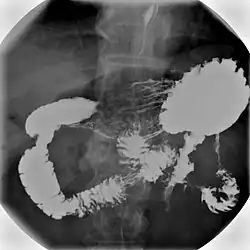

Various types of barium X-ray examinations are used to examine different parts of the gastrointestinal tract. These include barium swallow, barium meal, barium follow-through, and barium enema.[2] The barium swallow, barium meal, and barium follow-through are together also called an upper gastrointestinal series (or study), whereas the barium enema is called a lower gastrointestinal series (or study).[3] In upper gastrointestinal series examinations, the barium sulfate is mixed with water and swallowed orally, whereas in the lower gastrointestinal series (barium enema), the barium contrast agent is administered as an enema through a small tube inserted into the rectum.[2]

- Barium meal examinations are used to study the lower esophagus, stomach and duodenum.[2]

Barium meal

Intravenous injection of Buscopan (Hyoscine butylbromide) 20 mg or glucagon 0.3 mg is used to distend the stomach and slow down the emptying of the contrast into the duodenum.[13]

Right anterior oblique (RAO) view is used to demonstrate antrum and greater curve of stomach. Supine position is to demonstrate antrum and body of stomach. Left anterior oblique (LAO) view is used to see the lesser curve of stomach en face. This position is also used to check for gastroesophageal reflux when patient is asked to cough or swallow (water siphon test). Left lateral tilted with head up 45 degrees is used to demonstrate the fundus of the stomach.[13] To demonstrate the duodenal loop, the subject can lie down in prone position on a compression pad to prevent excessive barium flowing into the duodenal loop. Anterior view of duodenal loop can be seen at RAO position.[13] Duodenal cap can be visualised by taking images when subject lie down in prone position, RAO, supine, and then LAO positions or it can be seen on erect position with RAO and steep LAO views.[13] Total mucosal coating of the stomach is done by asking the subject to roll to the right side into a complete circle until RAO position. Arae gastriae in the antrum (fine reticular network of grooves) is visible if good coating is achieved.[13]